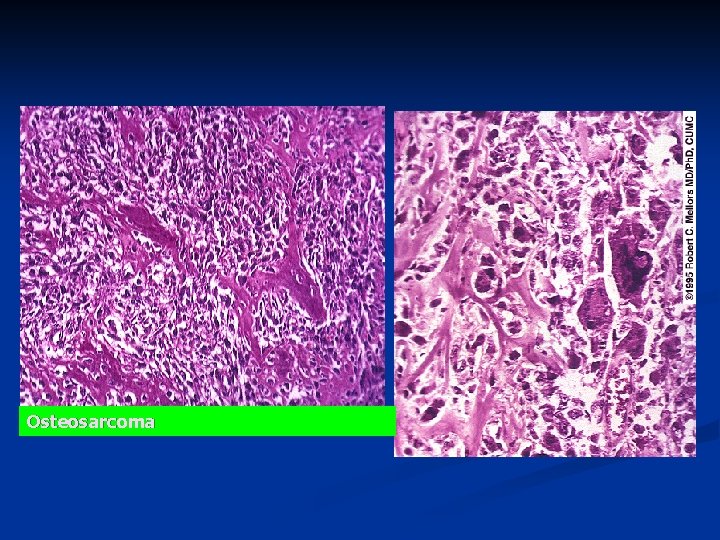

Microscopy n Proliferating malignant spindle- cell stroma n Osteoid or immature bone

Osteosarcoma

Osteosarcoma